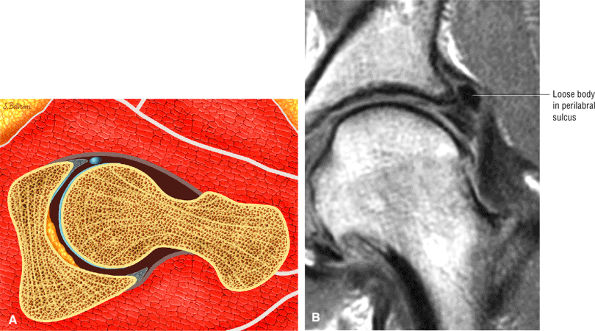

A transverse ligament-labral junction sulcus is a normal sulcus or recess that may be seen between the transverse ligament and the labrum either anteriorly (Fig. 3.62) or posteriorly (Fig. 3.63). The perilabral sulcus (Fig. 3.64) represents a normal space between the acetabular labrum and capsule visualized on coronal images. The capsule attaches directly to the osseous rim of the acetabulum. A normal sulcus may exist at the junction of the transverse ligament and labrum (see Fig. 3.62) on medial sagittal images. A normal perilabral sulcus is present on coronal images between the capsules and labrum and does not represent a pathologic detachment. This sulcus is a distinct and normal potential separation from the labrum (Fig. 3.65). The

perilabral sulcus is more conspicuous on MR arthrography. In comparison and contrast with the glenohumeral joint of the shoulder, the acetabular labrum of the hip is not critical in providing stability. However, it does maintain a role in creating the vacuum seal of the hip joint. -